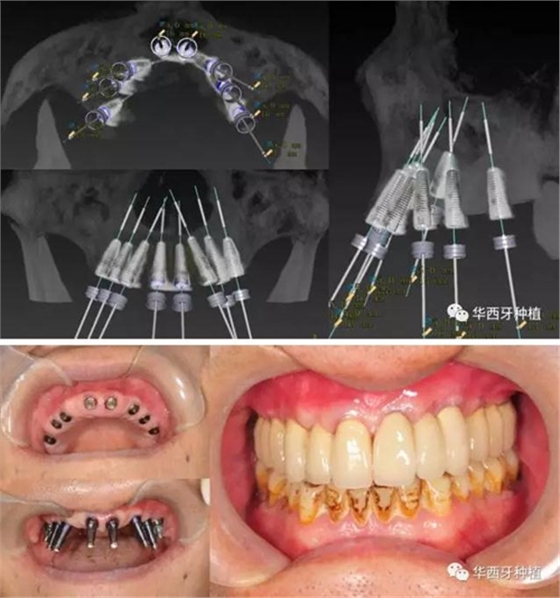

吳教授提到了使用數(shù)字化建模與導(dǎo)板的聯(lián)合應(yīng)用,不僅可以從設(shè)計(jì)上降低修復(fù)難度,便于在修復(fù)為導(dǎo)向的設(shè)計(jì)中種植體方向的確定,同時(shí)可以加入微創(chuàng)的手術(shù)方法,減輕術(shù)中創(chuàng)傷。

吳教授特別針對手術(shù)難度更大的all-on-four修復(fù)做了詳細(xì)的關(guān)于概念、設(shè)計(jì)、操作、修復(fù)的描述,首先是針對難度最大的手術(shù)環(huán)節(jié),就解剖、微創(chuàng)操作分別加以闡述。將他自己在臨床工作中的寶貴經(jīng)驗(yàn)分享給了大家。

對于傳統(tǒng)的all-on-four術(shù)式,吳教授加入了微創(chuàng)的指導(dǎo)思想,設(shè)計(jì)時(shí)同樣加入數(shù)字化三維重建與修復(fù)一體化設(shè)計(jì),增加了手術(shù)的可控性,同時(shí)極大減輕了患者的創(chuàng)傷程度,縮短了修復(fù)周期。

但是,他同時(shí)提到了此種修復(fù)方式操作難度要求很高,僅適合有經(jīng)驗(yàn)的種植醫(yī)生操作。